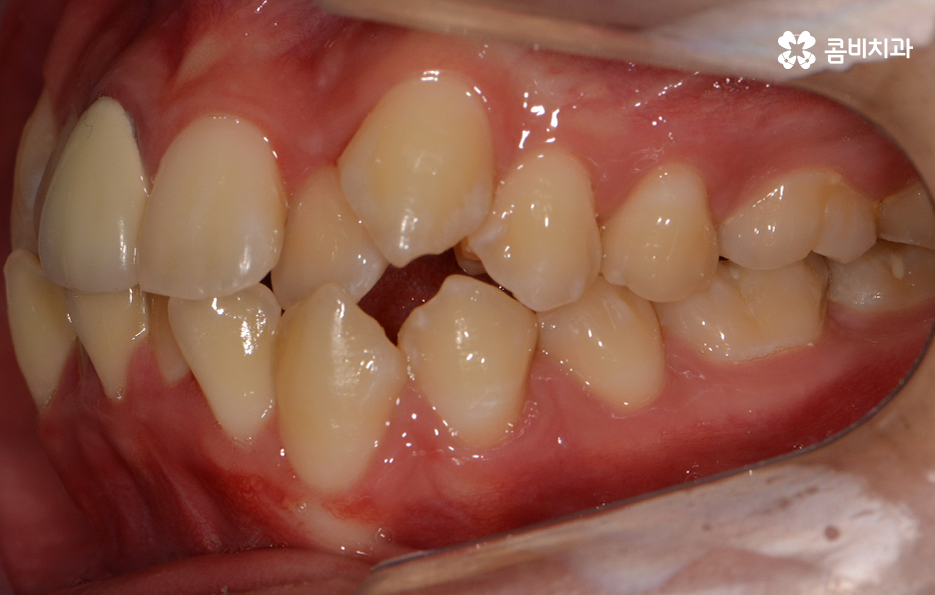

위 사례와 같이 턱이 좁은 경우에 사랑니 역시 제대로 맹출 될

공간이 부족한 경우가 많으며 사랑니가 누워서 자라는 경우에

어금니를 밀어내면서 치열을 더욱 망가지게 할 우려가 있으니

성인 이후에 치열이 불규칙해진 경우라면 사랑니의 체크가 꼭 필요할 수 있어요.

위 환자분의 케이스는 아랫니에 치아 2개를 발치하여

치아의 이동 공간을 확보하였고 발치교정이 진행될 때는

윗니와 아랫니 각각 2개씩 발치를 하는 경우가 많지만

위 사례는 치열, 교합 등을 고려할 때 아랫니 2개만

발치가 진행되었던 경우라고 볼 수 있어요.